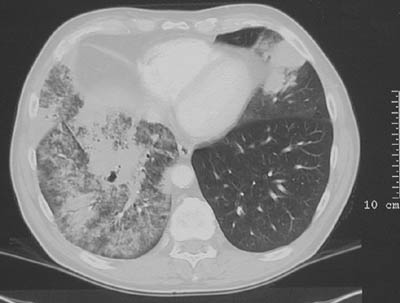

The chest CT scans in lung window above and bone window below demonstrate a very extensive bronchioloalveolar carcinoma involving most of the right lung. The tumor appears as large areas of consolidation resembling a pneumonia.